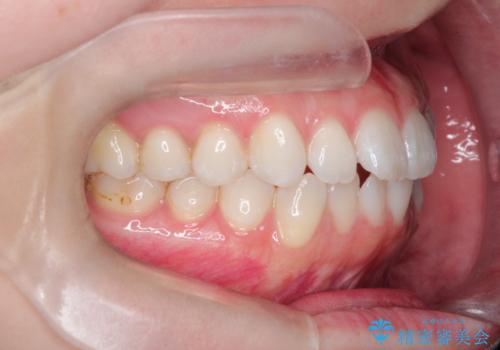

- 上下の前歯の凸凹が気になり、来院されました。

インビザラインで綺麗に仕上がり、満足していただきました。